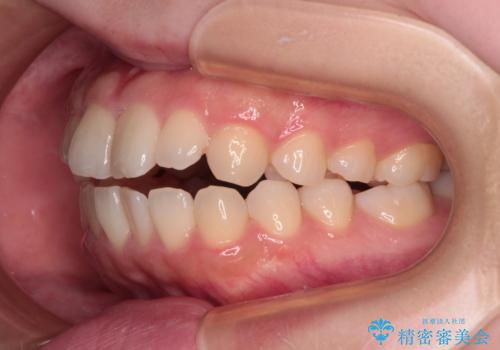

当初は舌のトレーニングをしっかりと行ってくださったおかげで、短い期間で治療を終えることができました。